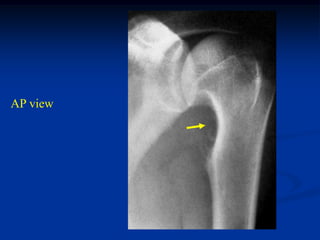

26 year male

periosteal chondroma

proximal humerus

CT scan